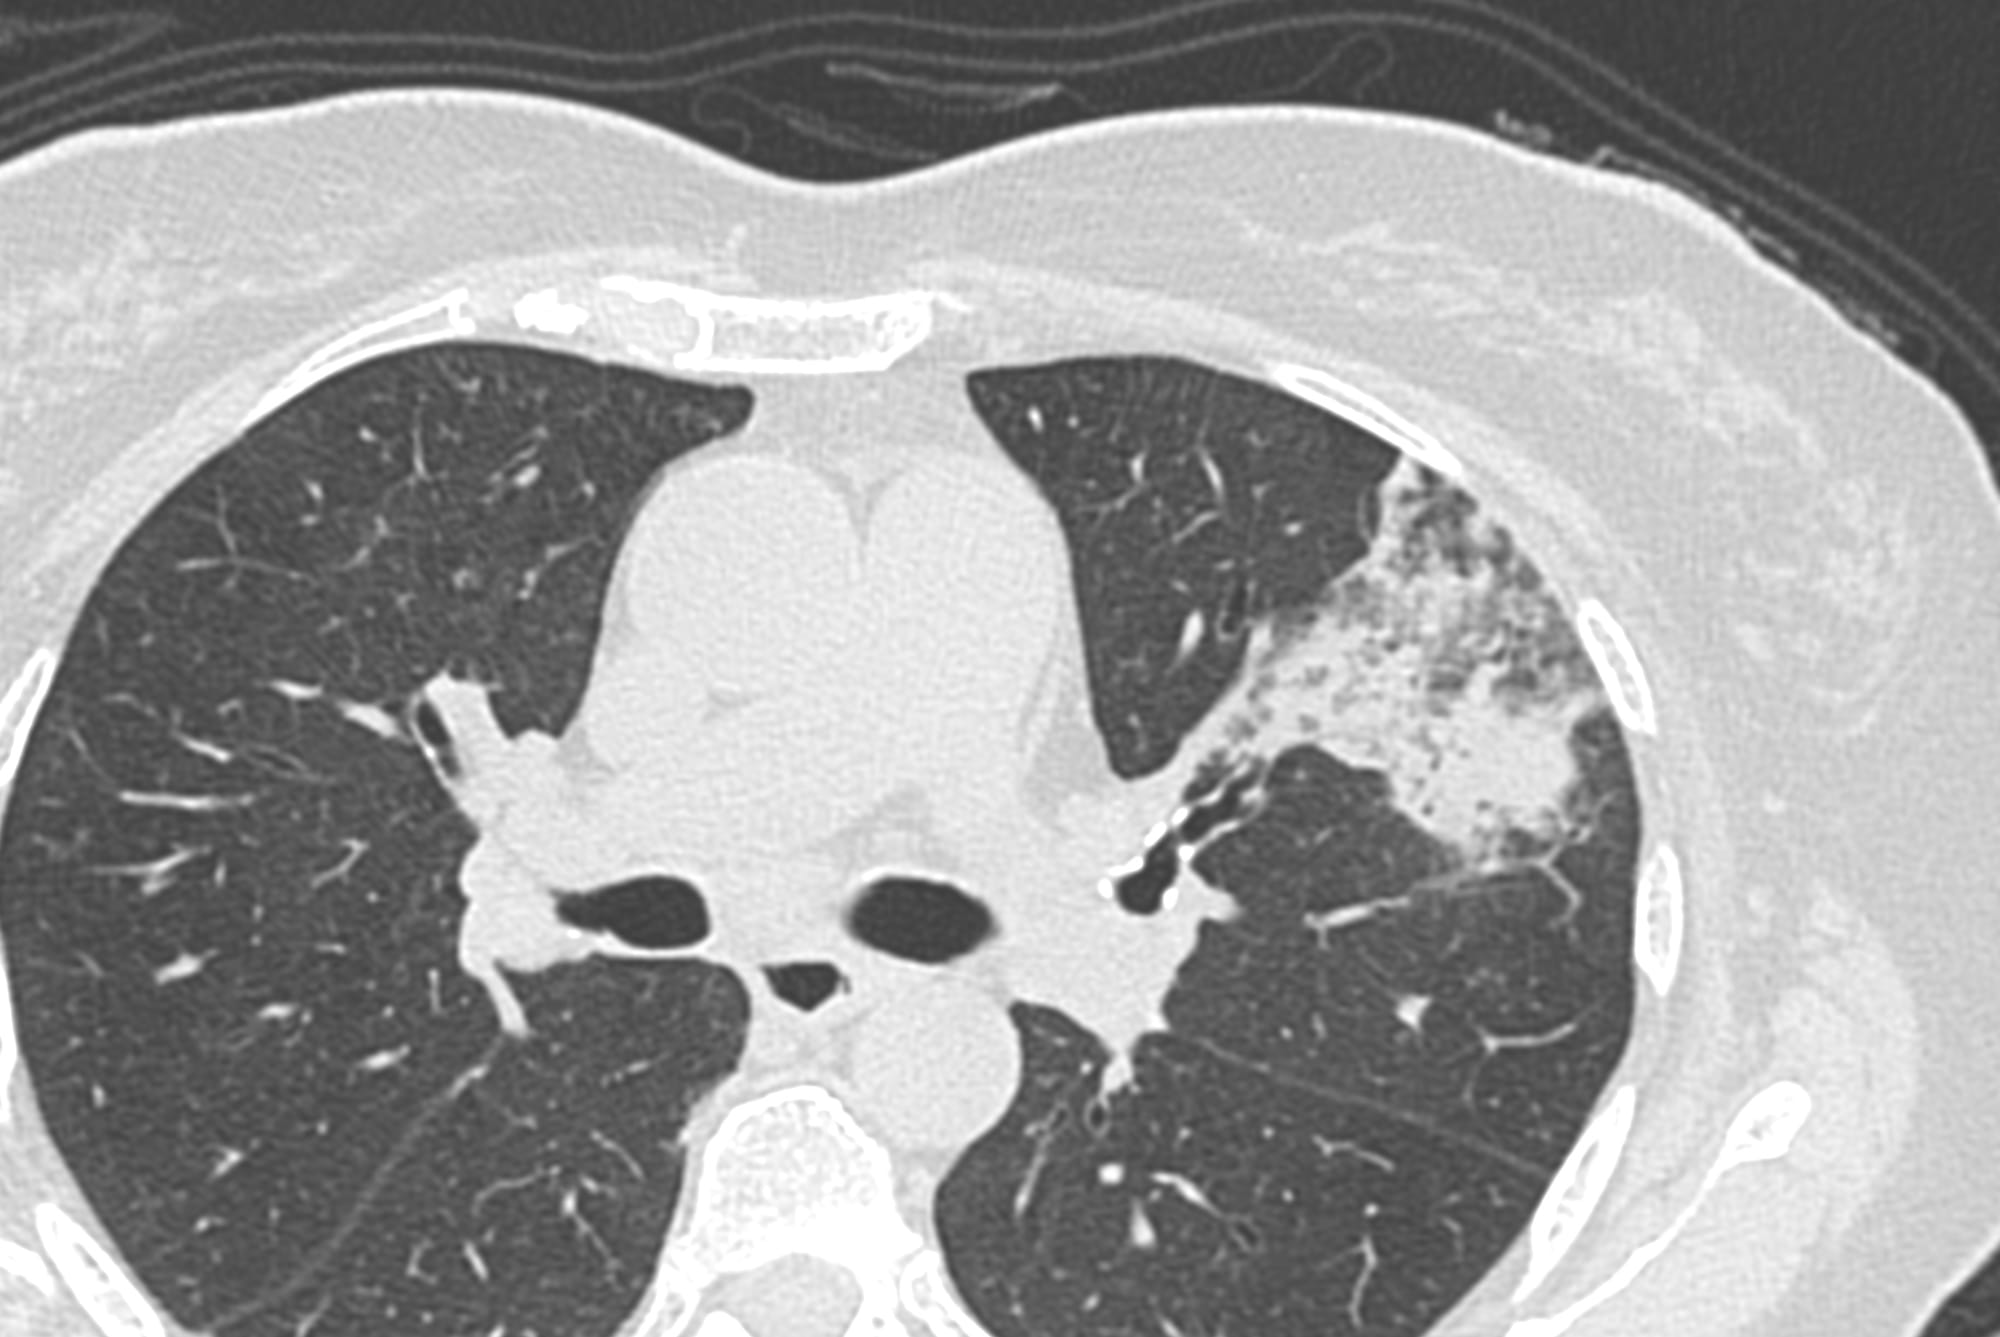

59-years old with fever and non-resolving consolidation

What would be your approach?

The video below describes the case and the reason for performing a biopsy parallel to the vessels and not perpendicular